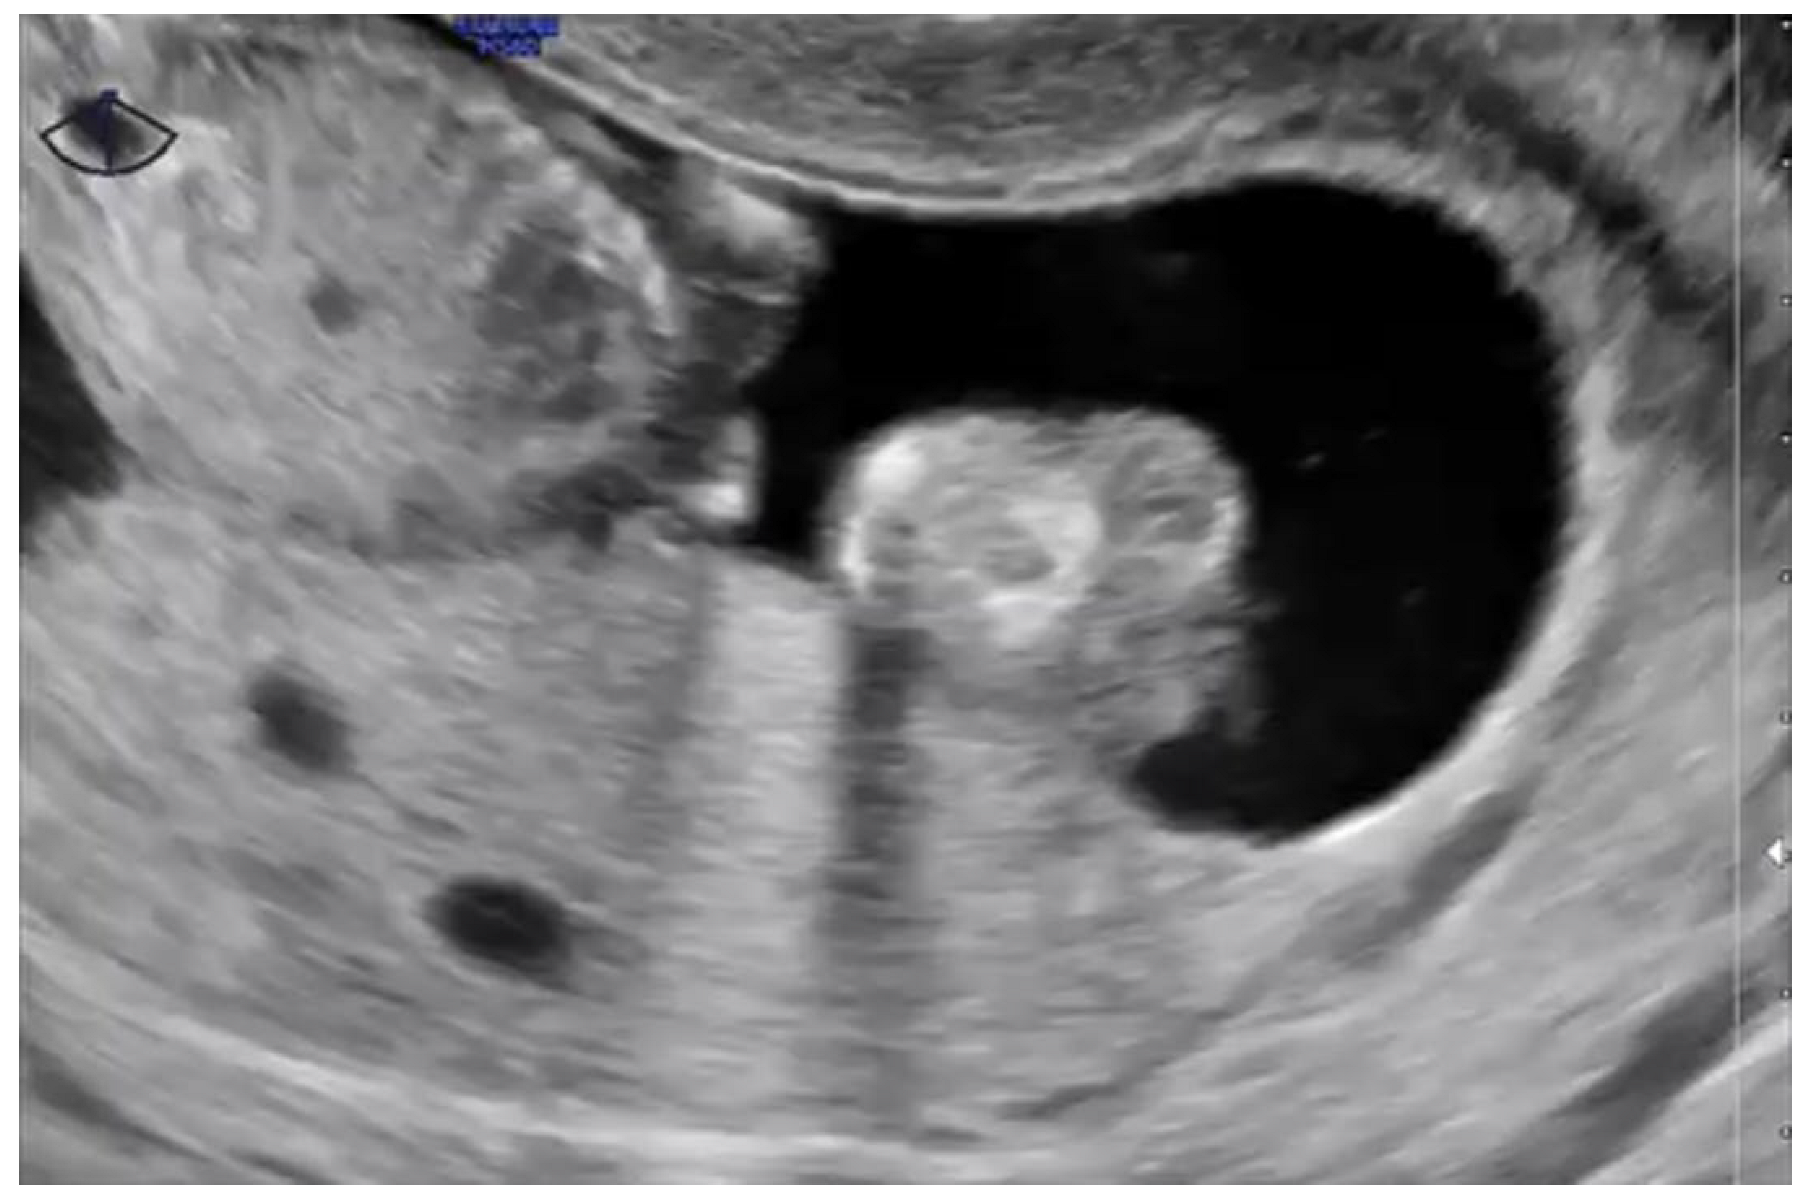

2.3. Pelvic Transvaginal Ultrasound

- Newhouse, I.; Spacey, A.; Scragg, B.; Szczepura, K. The diagnostic value and accuracy of ultrasound in diagnosing hydatidiform mole: A systematic review and meta-analysis of the literature. Radiography 2022, 28, 897–905. [Google Scholar] [CrossRef] [PubMed]

- Savage, J.L.; Maturen, K.E.; Mowers, E.L.; Pasque, K.B.; Wasnik, A.P.; Dalton, V.K.; Bell, J.D. Sonographic diagnosis of partial versus complete molar pregnancy: A reappraisal. J. Clin. Ultrasound 2017, 45, 72–78. [Google Scholar] [CrossRef] [PubMed]

- Braga, A.; Obeica, B.; Werner, H.; Sun, S.Y.; Amim Júnior, J.; Filho, J.R.; Júnior, E.A. A twin pregnancy with a hydatidiform mole and a coexisting live fetus: Prenatal diagnosis, treatment, and follow-up. J. Ultrason. 2017, 17, 299–305. [Google Scholar] [CrossRef]